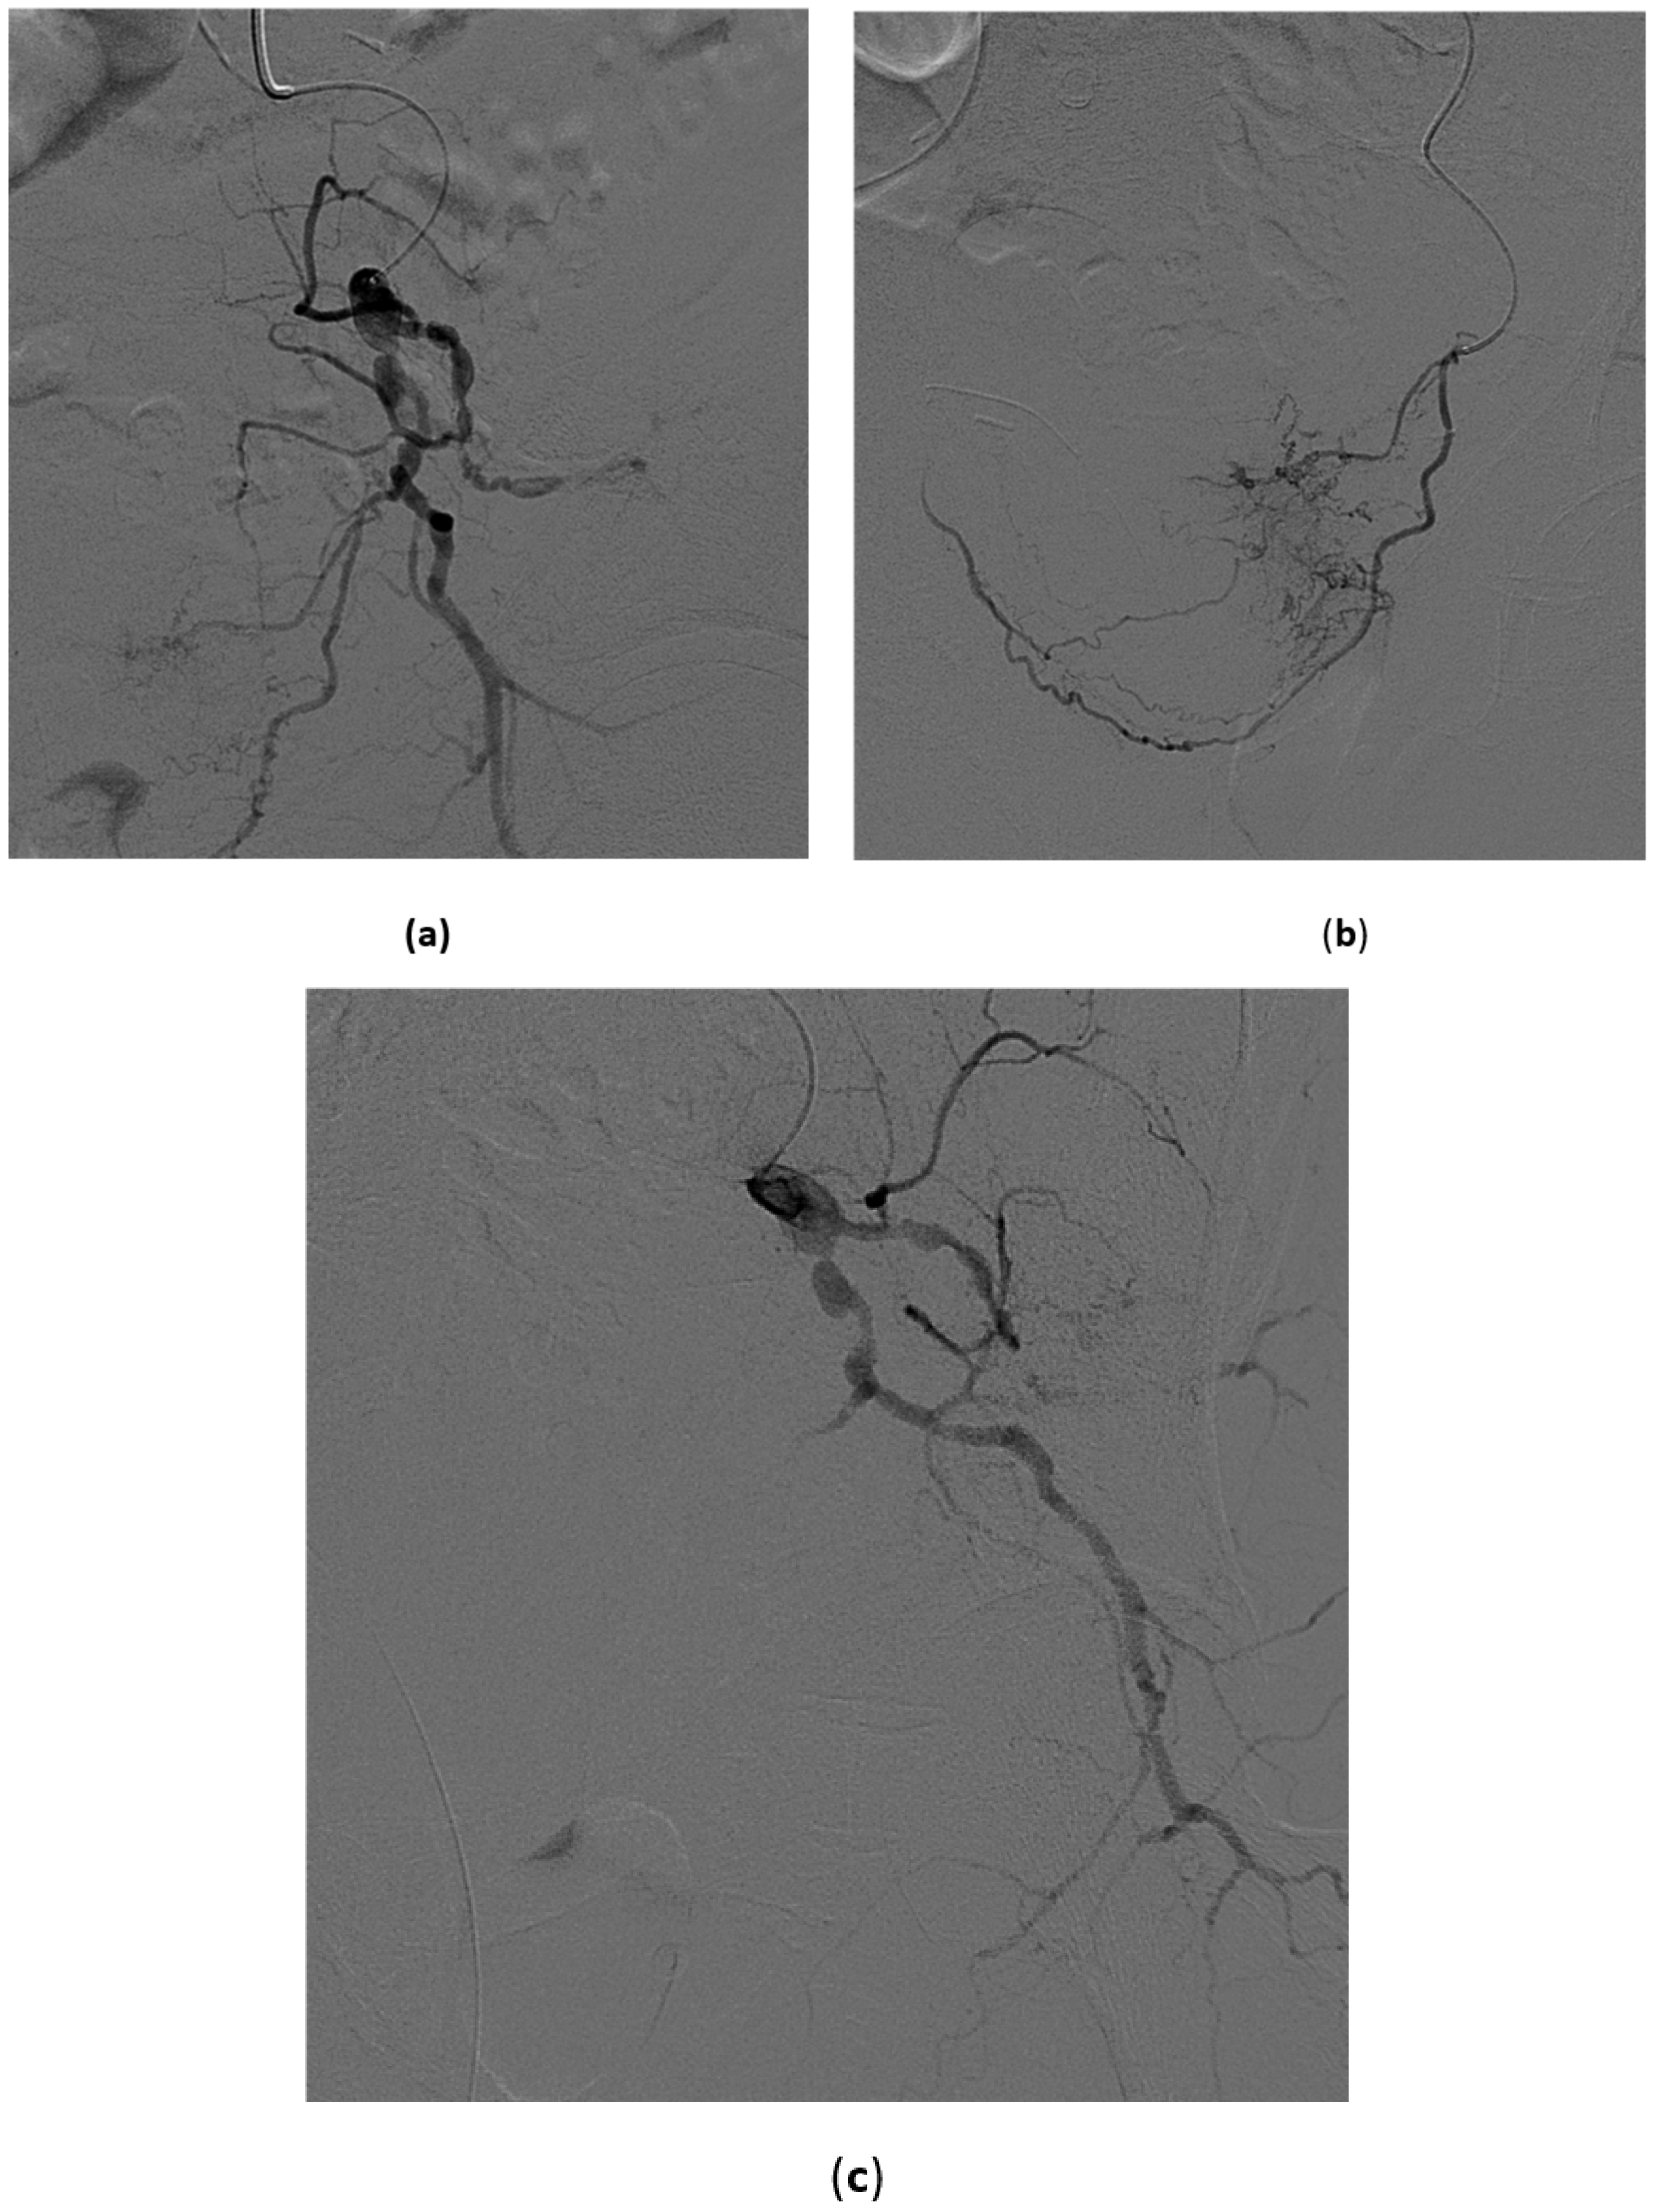

5.1. High-Flow Priapism

5.3. Treatment of High-Flow Priapism